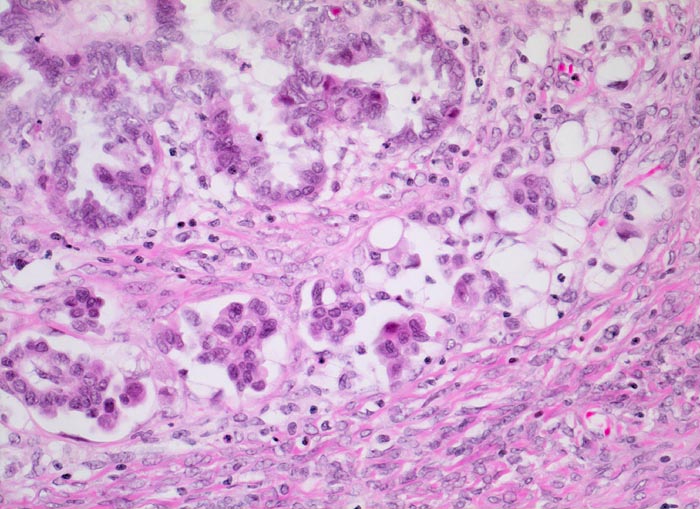

mikroinvasives serös papilläres Ovarialkarzinom

An umschriebener Stelle invadieren kleinere Zellgruppen und Einzelzellen das an dieser Stelle aufgelockerte Stroma.

Histologie

200